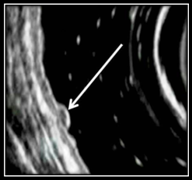

Рис. 4 (а, б). Эндосонографическая картина плосковозвышающейся формы НЭО желудка

В плосковозвышающейся форме НЭО выделены два типа:

1) 1-й тип — возвышающееся образование гипоэхогенной плотности размером до 5 мм, локализующееся на уровне мышечной пластинки слизистой оболочки (рис. 4а);

2) 2-й тип — локальное утолщение мышечной пластинки слизистой оболочки изоэхогенной плотности веретенообразной формы размером до 5 мм (рис. 4б).